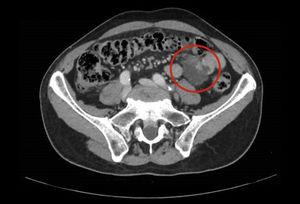

Varón de 71 años con antecedente de leucemia linfocítica. En una tomografía computarizada control, se evidenció una lesión de 30 x 35 mm dependiente de un asa de intestino delgado (fig. 1) sospechosa de tumor del estroma gastrointestinal (GIST).